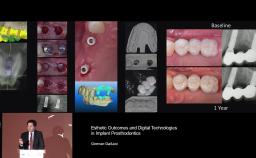

German Gallucci

Boston, United States